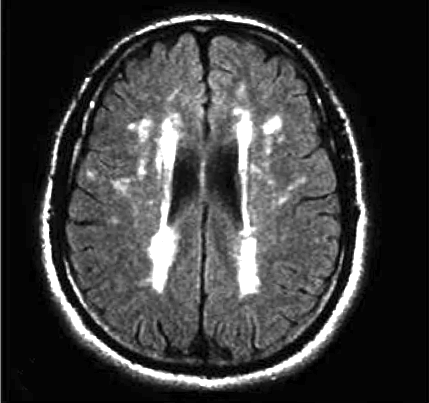

Em 1987, Hachinski introduziu o conceito de leucoaraiose (do grego leuko = branco, e araios = redução) para se referir a uma alteração nas imagens da Tomografia Computadorizada e da Ressonância Magnética cerebral na substância branca dos hemisférios cerebrais. As lesões podem ser puntiformes, extensas, focais ou difusas. Com este termo, não foi proposta nenhuma correlação clínica ou patológica, apenas foram denominadas imagens anormais relativamente frequentes. Trata-se, portanto, de um termo de neuroimagem descritivo, que pode estar relacionado a diversas situações clínicas e patológicas. Além disso, é um termo heterogêneo, já que inclui diversos tipos de alterações morfológicas.

A progressão da leucoaraiose tende a seguir um padrão geral. Inicialmente, se observam as lesões periventriculares em direção à borda dos ventrículos laterais, (Fig.1) se estendendo, conforme a gravidade deste fenômeno, ao redor dos mesmos (Fig.2).

Tal como mencionamos, a Leucoaraiose se refere a certas alterações que podem ser detectadas mediante imagens de Tomografia Computadorizada e Ressonância Nuclear cerebral, que consistem nas regiões de hipodensidade ou de hiperintensidade, respectivamente.

Entre as duas, a Imagem por Ressonância Magnética do encéfalo, que inclui sequências ponderadas em T2 e FLAIR, é a técnica mais frequente na avaliação da Leucoaraiose.

A escala qualitativa de Fazekas (Fig.3) é a mais utilizada para determinar a magnitude das lesões da substância branca em IRM, classificando:

– grau 0: com ausência de lesão;

– grau 1: com a existência de lesões focais;

– grau 2: com o começo da confluência de lesões;

– grau 3: com lesões difusas, que compreendem regiões inteiras.